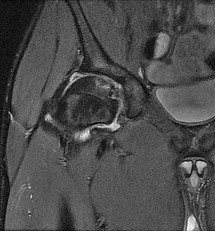

The plain radiographs and MR image shown in Figures 37a through 37c indicate which condition?

- Cam-type femoroacetabular impingement with an acetabular labral tear

Which condition would you expect to identify during a hip arthroscopy procedure for this patient based on the radiographic findings in Figures 37a through 37c?

- Articular cartilage delamination

The radiographic studies reveal both acetabular dysplasia and cam-type femoroacetabular impingement. The MR image shows an acetabular labral tear. Structural abnormalities of the hip, including femoroacetabular impingement, have commonly been identified in association with labral tears. Disruption of the ligamentum teres is not associated with impingement conditions in the absence of trauma.

The patient has acetabular dysplasia with a decreased lateral center-edge angle and also has visible cam-type femoroacetabular impingement. The common pathway for joint degeneration in hips with cam-type femoral head anatomy includes the development of cartilage damage in the anterior or superolateral aspects of the acetabular cartilage. Paralabral cysts may be seen more commonly in association with acetabular dysplasia, although the patient’s radiographs did not demonstrate substantial cystic changes. Osteochondral loose bodies and ligamentum teres ruptures can be seen at arthroscopy in a small number of cases.

There are several proposed roles of the acetabular labrum. It can increase the depth of the acetabular socket by as much as 21% to 28%. Roles of the acetabular labrum include joint lubrication, shock absorption, and pressure distribution. Recent studies assessing the effects of loading on joint stability for both normal and dysplastic hips did not demonstrate a substantial role of the labrum in differences in loading. Although joint stability might be improved following surgical repair, acetabular dysplasia is not likely to be resolved with acetabular labral repair alone.